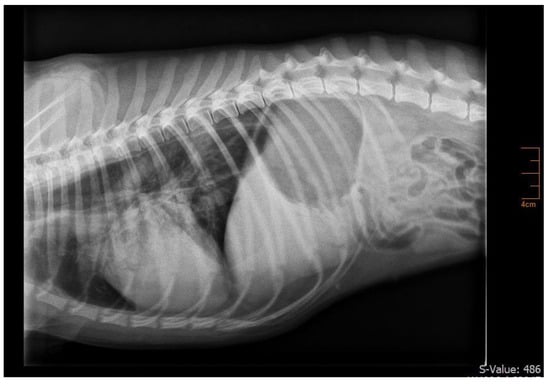

2. Case Presentation